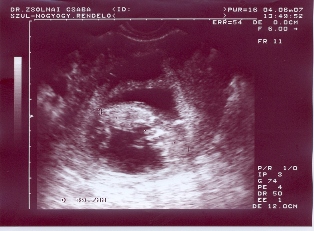

Sziasztrok!

Ezek az én drágám a kis ficergék!minden ok velük és velem is!Zárt méhszáj,mehetek tornázni és úszni is!

59mm-es mindkettő baba!Nyakiredő is ok volt!Genetikaira nem kell mennem!Hurrá!!!!!!